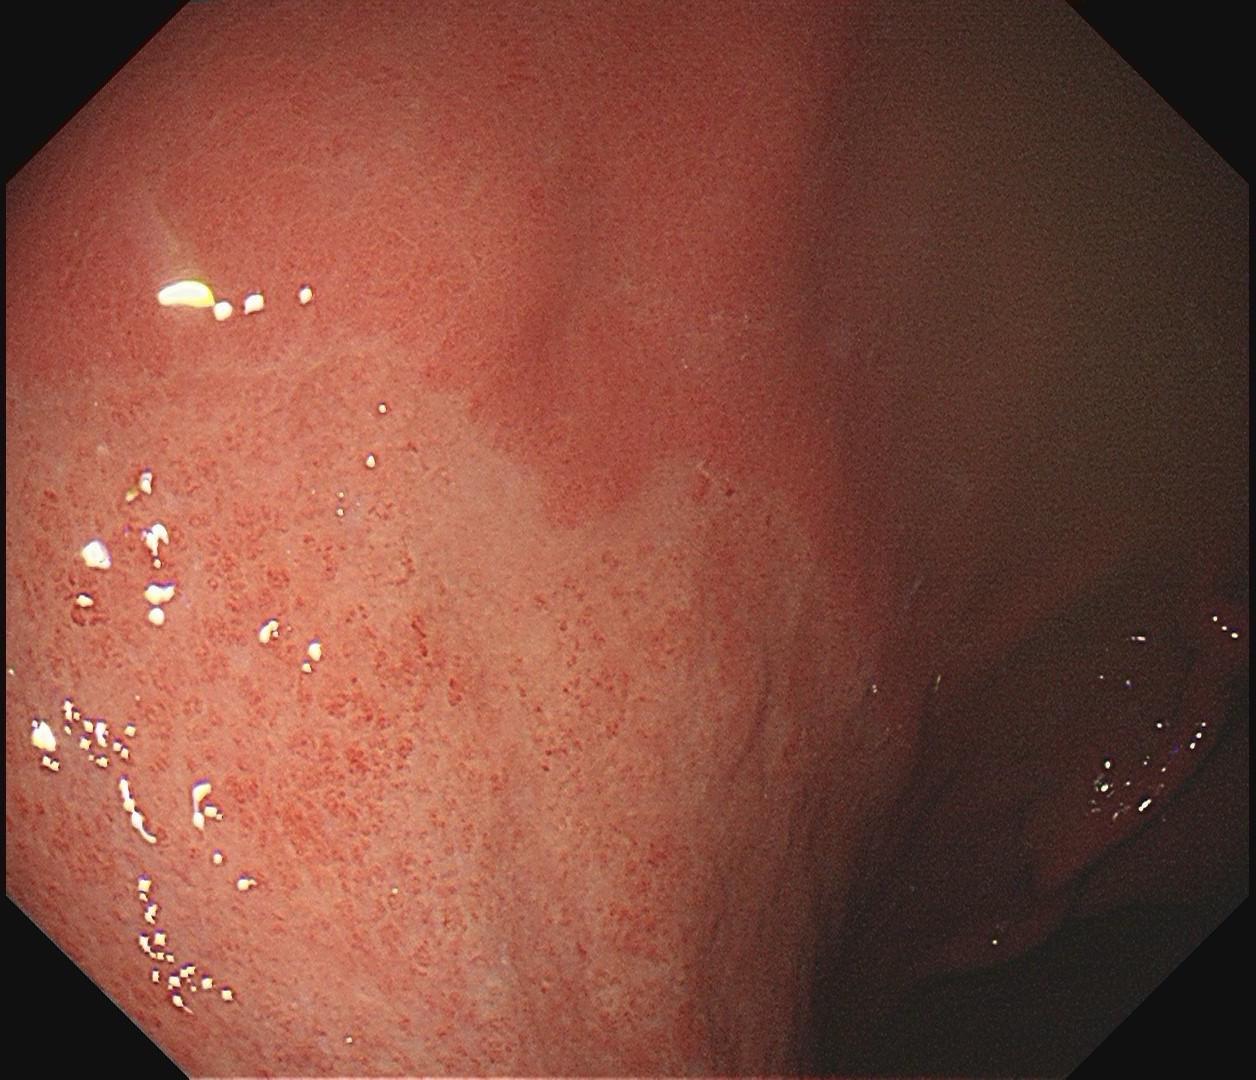

男,61岁,胃巨大褪色调病变。答案在最后一张图片,你猜对了吗? 患者因上腹部饱胀行胃镜检查,Hp阴性背景,胃窦至贲门下见一巨大褪色调病变,边界清晰,病变相对表浅,未见明显溃疡及隆起,胃壁较柔软,充气顺应性佳,予多点活检确诊,拟外科手术行全胃切除。做这么多年胃镜,还是第一次遇到这样的……